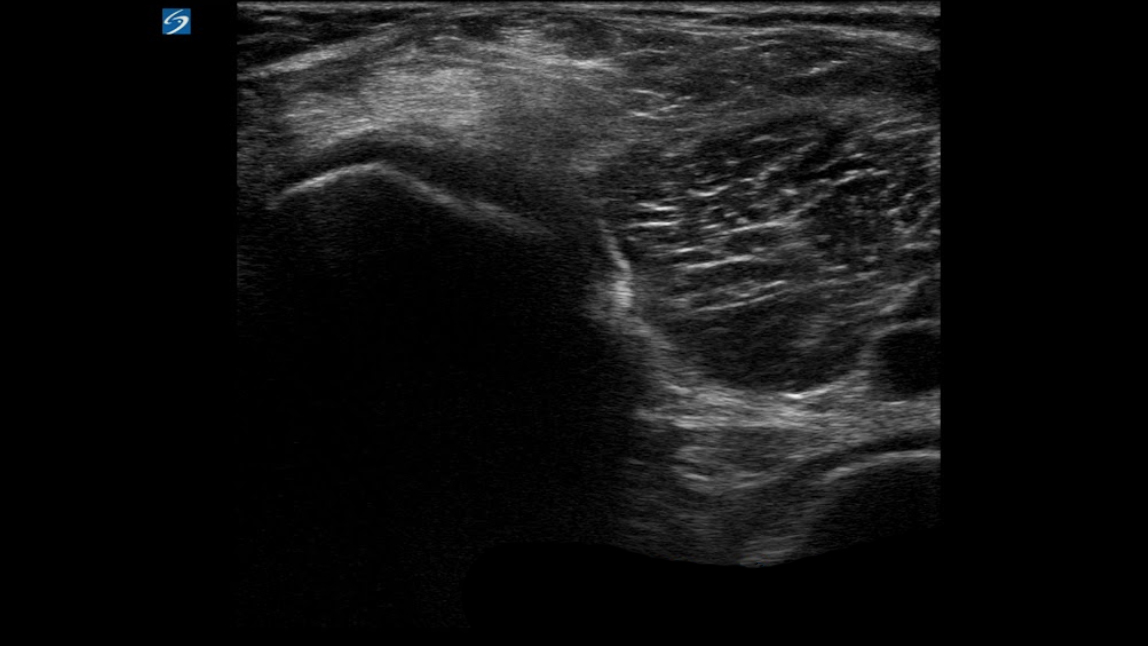

Knee Baker's Cyst Anatomy 6 Image